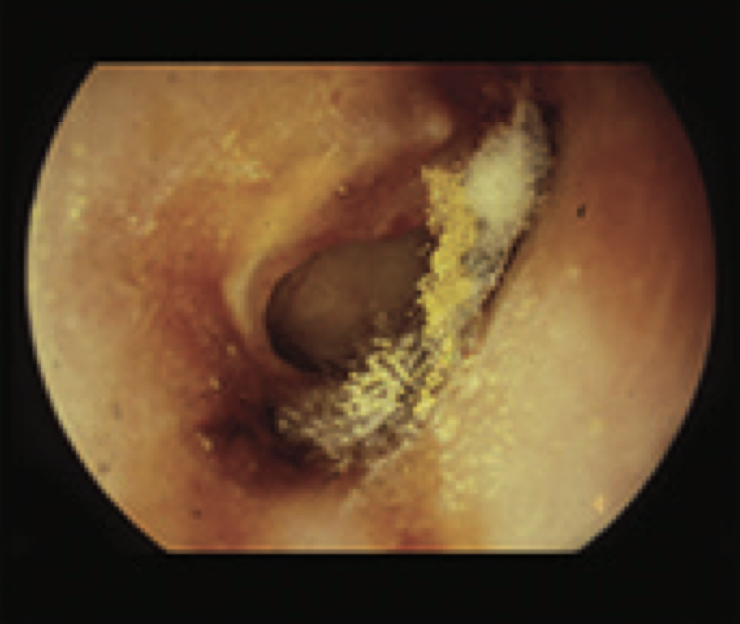

11

Q

What is this?

A

Wet cholesteatoma

- TM with tympanosclerosis

- large attic perforation